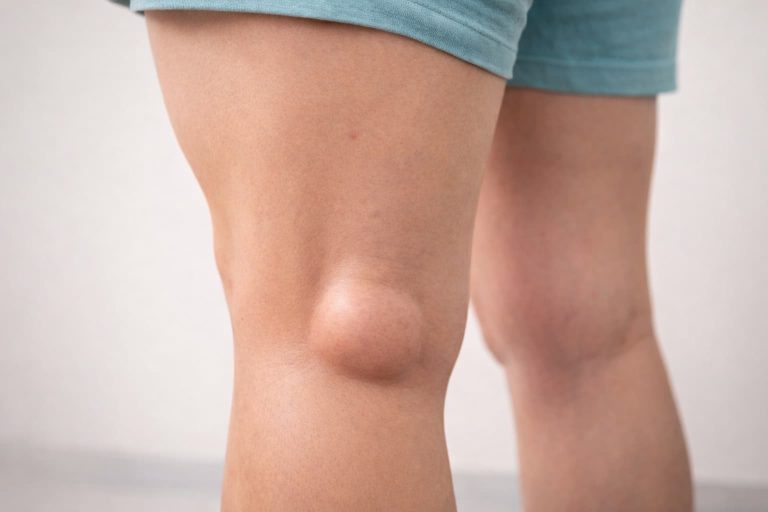

Simptomele gonartrozei evoluează progresiv și pot include:

- umflarea genunchiului

- deformarea genunchiului în stadii avansate